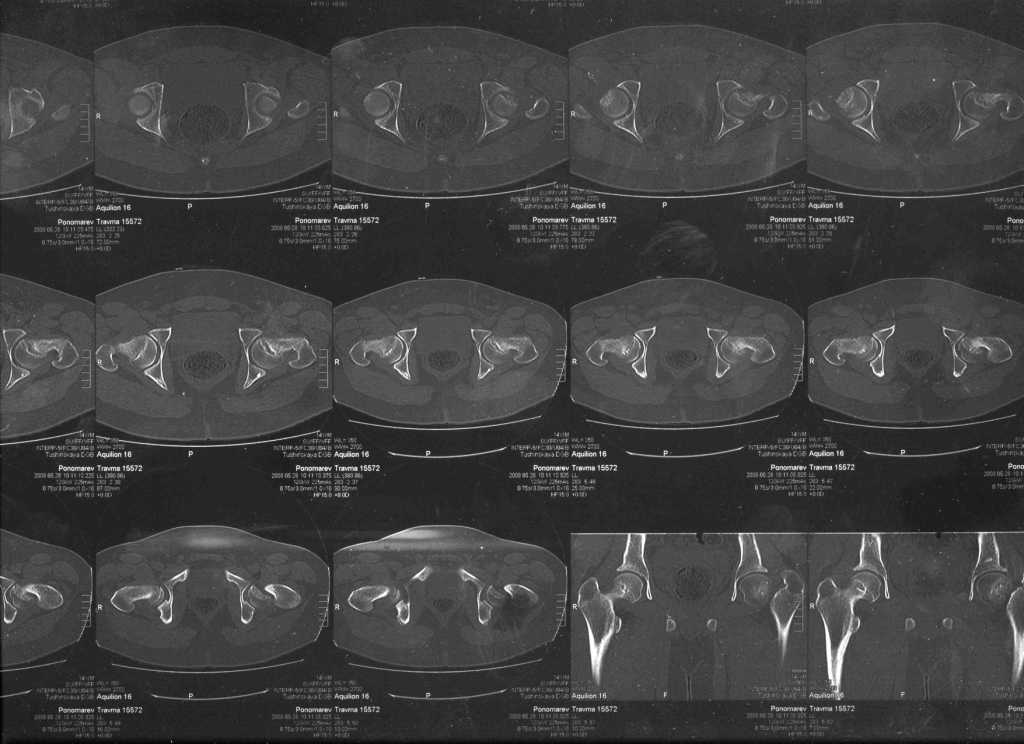

Ребёнок 14 лет. Весом под центнер. Имеющаяся рентгенологическая деформация деформация - на момент поступления. Госпитализирован ребёнок 14 лет. Мальчик, мягко говоря, крупный, гиперстенического типа сложения, ближе к десантнику. Весит 95 кг. Ожирение 2-й степени. Со слов больного - испытывает дискомфорт в области тазобедренного сустава в течение 3-х месяцев. На рентгенограммах - положение дел на момент поступления - конец мая. Укорочение конечности на 1,5 см. Ограничение внутренней ротации. Ходит, едва заметно прихрамывая на больную ногу. Эндокринологический статус находится в стадии обследования. Выполнена рентгенография в стандартных укладках, спиральная КТГ.Ясное дело, головка бедра <ушла> вниз и кзади. Пытающаяся <поймать> её шейка варизировалась и исполнила ретроверсию, создав изгиб во фронтальной плоскости. На рентгеноскопии - подвижность головки не определяется. Мальчик имеет далеко идущие планы на обустройство собственной жизни и образование. Крайне негативно относится к длительной иммобилизации и консервативному лечению. Загодя не согласен со снижением качества жизни в процессе лечения. Мнения коллег относительно дальнейшего лечения разделились. Успешность репозиции головки под наркозом - сомнительная в связи с имеющейся деформацией шейки бедра. Одни склоняются к тактике невмешательства - разгрузка больной конечности, ФЗТ , массаж, и т.д. Предлагают ждать завершения процесса <сползания> головки в условиях полной разгрузки, <тянуть> сустав до эндопротезирования как можно дольше. Другая группа коллег предлагает немедленную стабилизацию головки, что, кажется, правильно. Принимая во внимание анатомическое соотношение головки и шейки бедра, способ остеосинтеза так же вызвал массу споров, не приведших к единому и окончательному мнению. Пока дискуссия остановилась на стабилизации спицами Бека под контролем ЭОП, возможно с применением электродов для проведения электростимуляции слабыми импульсными токами. Техника проведения спиц, однозначно, будет сопряжена с техническими трудностями, обусловленными имеющейся деформацией шейки. Как бы Вы поступили, коллеги, в данной ситуации?Заранее спасибо. И прошу прощения за качество спимков. Буду отправлять их по очереди.

Здравствуйте Данил. По представленным рентгенограммамам и кт срезам Вы имеете дело хронической, стабильной формой ЮЭГБК. Шеечно- эпифизарная деформация выраженная, эпифиз отклонён кзади более чем на 70 градусов, практически до упора в межвертельную ямку, что характеризует её как тяжёлую степень. В выборе метода лечения мы придерживаемся следующей схемы: